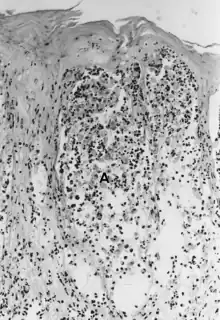

| Foot-and-mouth disease - acantholysis in a sample of a skin vesicle: Necrosis of the stratum spinosum can be observed, and keratinocytes floating in the vesicular fluid (spongiosa). | |

Acantholysis is the loss of intercellular connections, such as desmosomes, resulting in loss of cohesion between keratinocytes,[1] seen in diseases such as pemphigus vulgaris.[2] It is absent in bullous pemphigoid, making it useful for differential diagnosis.